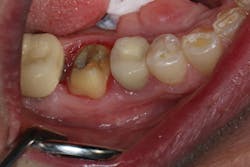

In the first case, a tooth with a subgingival margin preparation has been cleaned with an ultrasonic scaler and is gently dried in preparation for cementation. Note how the margin goes deeper subgingivally on the distolingual (figure 1). With TheraCem, a clean, prepped dentin or enamel surface is all that is needed to achieve excellent bond strengths, with the added benefit of sustained calcium and fluoride release. While TheraCem forms a strong bond to most substrates, including zirconia, a zirconia primer is still used prior to try-in to achieve optimal bond strength and prevent salivary contamination of the zirconia surface (figure 2).

Figure 1: Cleaned and prepared tooth